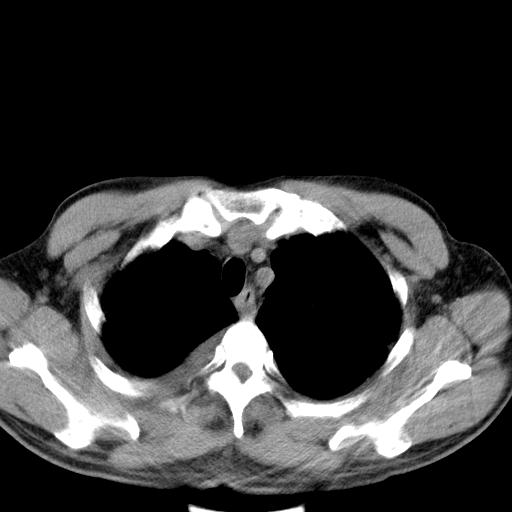

以下是引用zjzjr在2010-3-21 17:39:00的发言:[br]右下中心型肺癌并阻塞性肺炎/不张,纵膈淋巴结肿大,右侧大量胸腔积液,左侧少量胸腔积液

以下是引用zxl51642在2010-3-21 17:06:00的发言:[br]右下中心型肺癌并阻塞性肺炎/不张,纵膈淋巴结肿大,右侧大量胸腔积液,左侧少量胸腔积液,少量腹水。建议纤维支气管镜进一步检查。